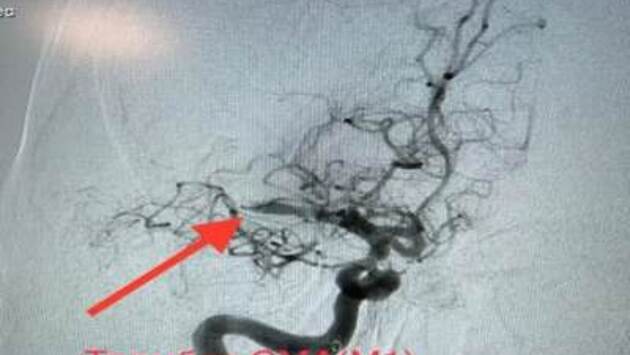

Медики из сосудистого центра Воскресенской больницы спасли 54-летнюю пациентку, у которой был диагностирован обширный инсульт, сообщает пресс-служба министерства здравоохранения Московской области. Женщину доставила в больницу скорая медицинская помощь. Пациентка жаловалась на головокружение, слабость и онемение в левой руке и ноге. Обследование показало, что у нее острый тромбоз средней мозговой артерии и критическое сужение правой внутренней и наружной сонной артерии. Медики предупреждают, что если в данном случае не предпринять меры, то это может привести к инвалидности, нарушению двигательной активности, речи и другим последствиям. «Нами было принято решение о проведении экстренной операции. Пациентке выполнили тромбоэкстракцию, то есть удалили тромб из средней мозговой артерии через небольшой прокол в ноге. После этого было проведено стентирование внутренней сонной артерии справа. Операция проведена эндоваскулярно с помощью ангиографической установки», - отметил заведующий сосудистым центром Воскресенской больницы Гурген Айвазян. Специалист подчеркнул, что плюсом этой методики проведения операции является то, что вмешательство проводится без разрезов и наркоза. Операция прошла успешно. Сейчас женщина чувствует себя хорошо и продолжает лечение в стационаре.